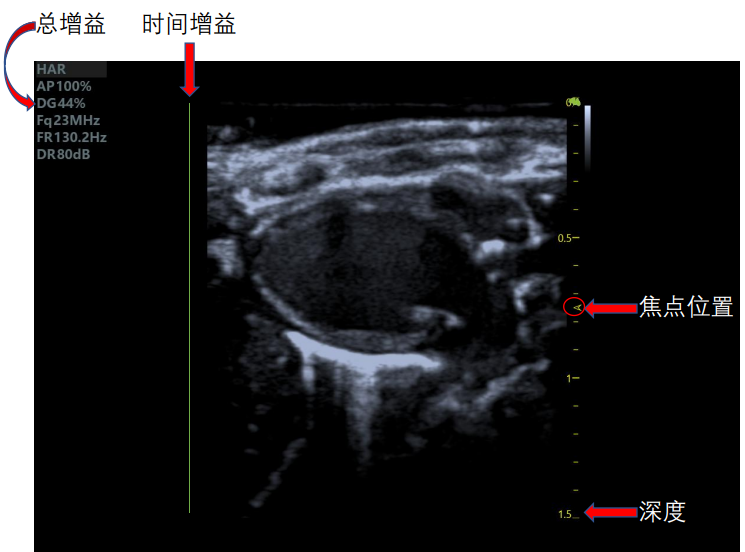

超聲波因其頻率超過了人耳的聽覺范圍所限,所以稱之為超聲波。利用人體超聲產生的波在人體內傳播時,通過示波屏顯示體內各種器官和組織對超聲的反射和減弱規律來診斷疾病的一種方法。 超聲波具有良好的方向性,在人體內傳播過程中,遇到密度不同的組織器官,即有反射、折射和吸收等現象產生。 根據示波屏上顯示的回波距離、弱強和多少,以及衰減是否明顯,可以顯示體內某些臟器的活動功能,并能確切鑒別出組織器官是否含有液體或氣體,或一些實質性組織。 產生波分為多種波形,小動物超聲成像系統主要用于M型法,其主要是根據體內心臟等結構活動,記錄其與胸壁間的回聲距離變化曲線,從曲線圖上清晰認出心臟的相關特征,可用于診斷多種心臟疾病。 如何得到一個準確的數據及好看的心臟切面圖?接下來請看仔細: 一個好看的心臟切面圖需要注意超聲掃查的切面選取及手法、總時間及時間增益、焦點位置、深度。 1.心臟切面手法:

4.增益調節:增益調節至看到組織且不刺眼即可,增大增益會使圖像更加明亮清晰,降低增益,可減少噪聲,使圖像更清晰。